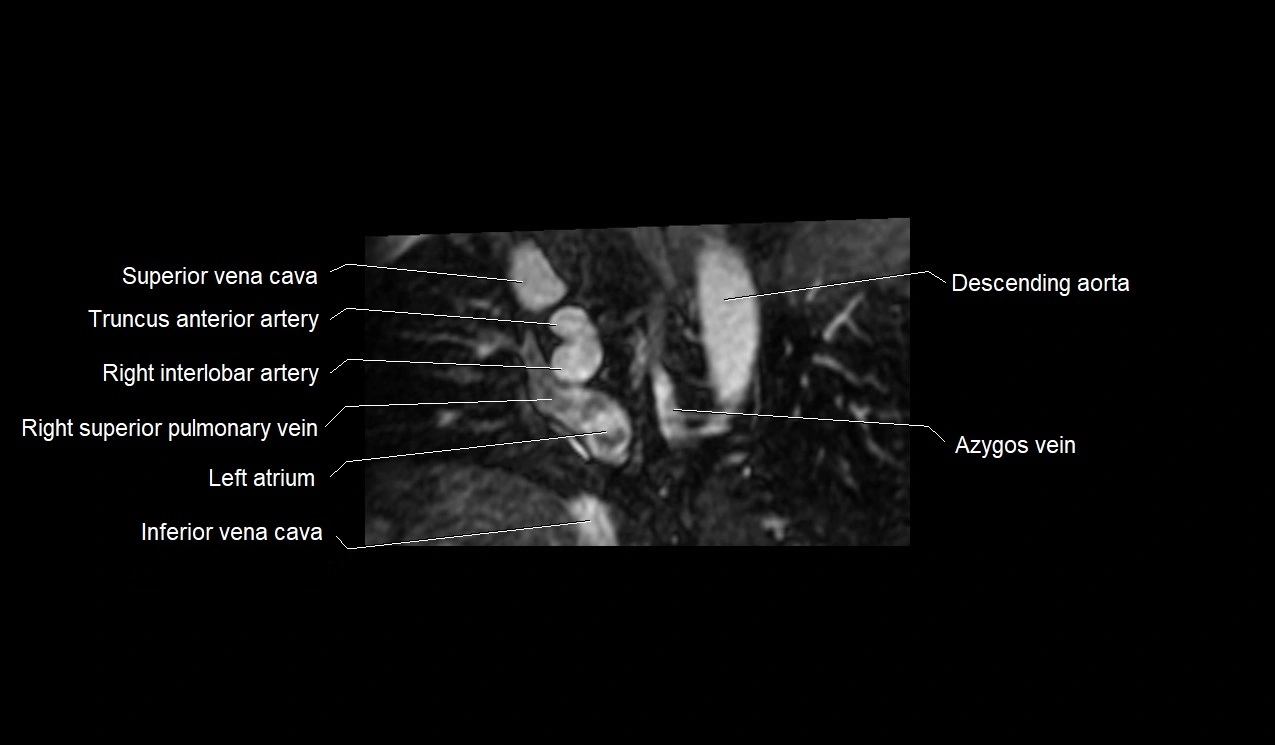

MRI image